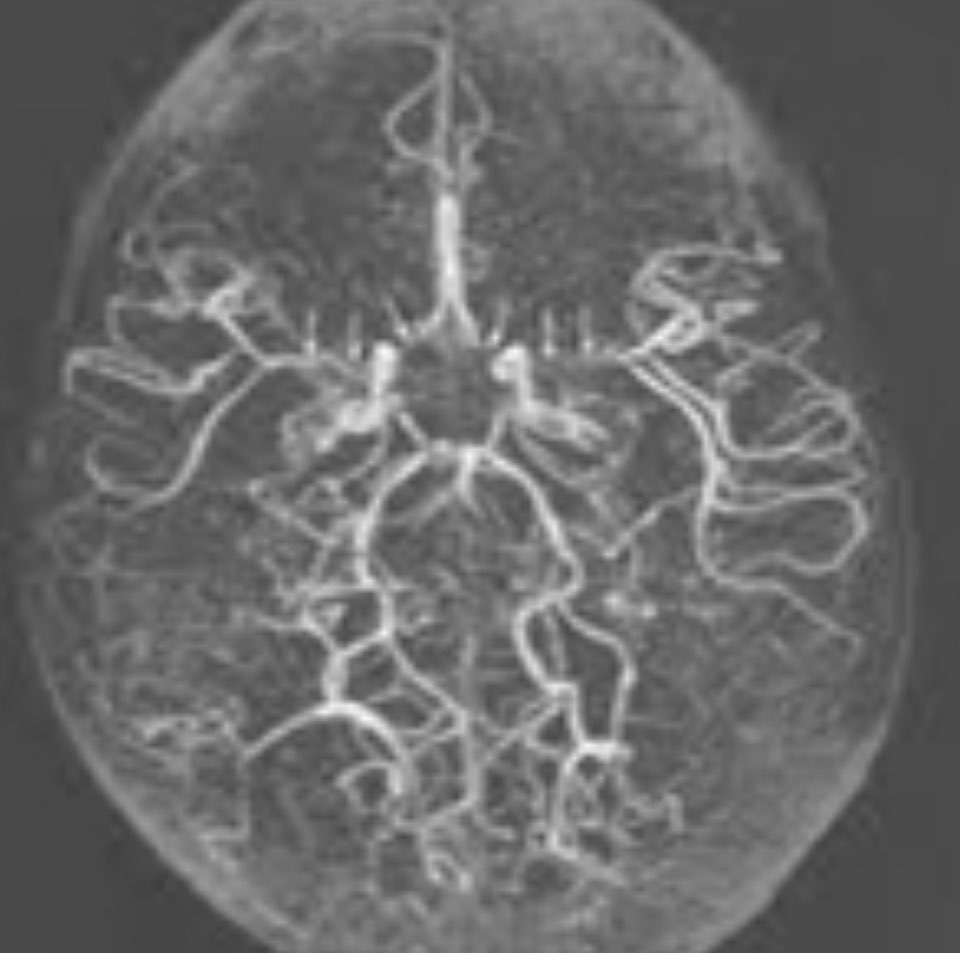

모야모야병은 뇌혈관 질환으로, 중대뇌동맥이 점차 좁아지거나 막히는 상태를 말합니다.

"모야모야"라는 용어는 일본어로 '연기처럼 흐릿하게'라는 뜻으로, 혈관이 비정상적으로 확장되어 연기처럼 보이는 모습에서 유래되었습니다.